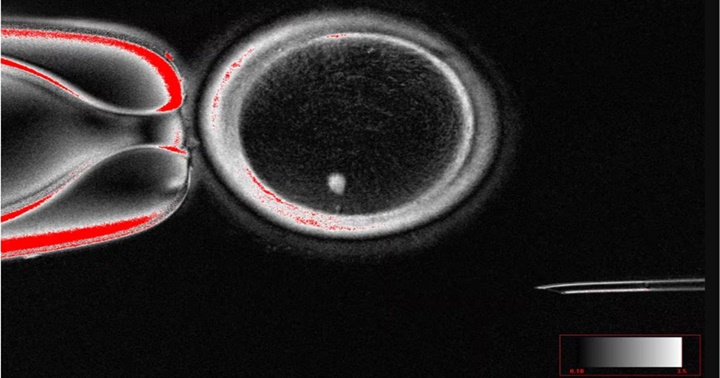

Los investigadores emplearon una técnica conocida como Transferencia Nuclear de Células Somáticas (SCNT), la misma que se utiliza para la clonación y que hizo posible la oveja Dolly en 1996. Tomaron el núcleo de una célula de piel, con sus 46 cromosomas, y lo introdujeron en el óvulo de una donante al que antes habían extraído su núcleo. Si ese óvulo se fecundase con un espermatozoide, daría lugar a un embrión con tres pares de cromosomas, inviable. Para evitarlo, indujeron un proceso que bautizaron como mitomeiosis que engaña a la célula para que se divida sin antes haber duplicado su ADN, descartando un par de cromosomas y haciendo que el óvulo sea funcional.

Con este proceso, produjeron 82 ovocitos funcionales que después fertilizaron en el laboratorio. De estos óvulos, solo el 9% se desarrolló hasta los seis días, el punto en el que el embrión se transferiría al útero en un tratamiento de fertilización in vitro, pero en el experimento ya no se continuó con el cultivo y se descartaron.